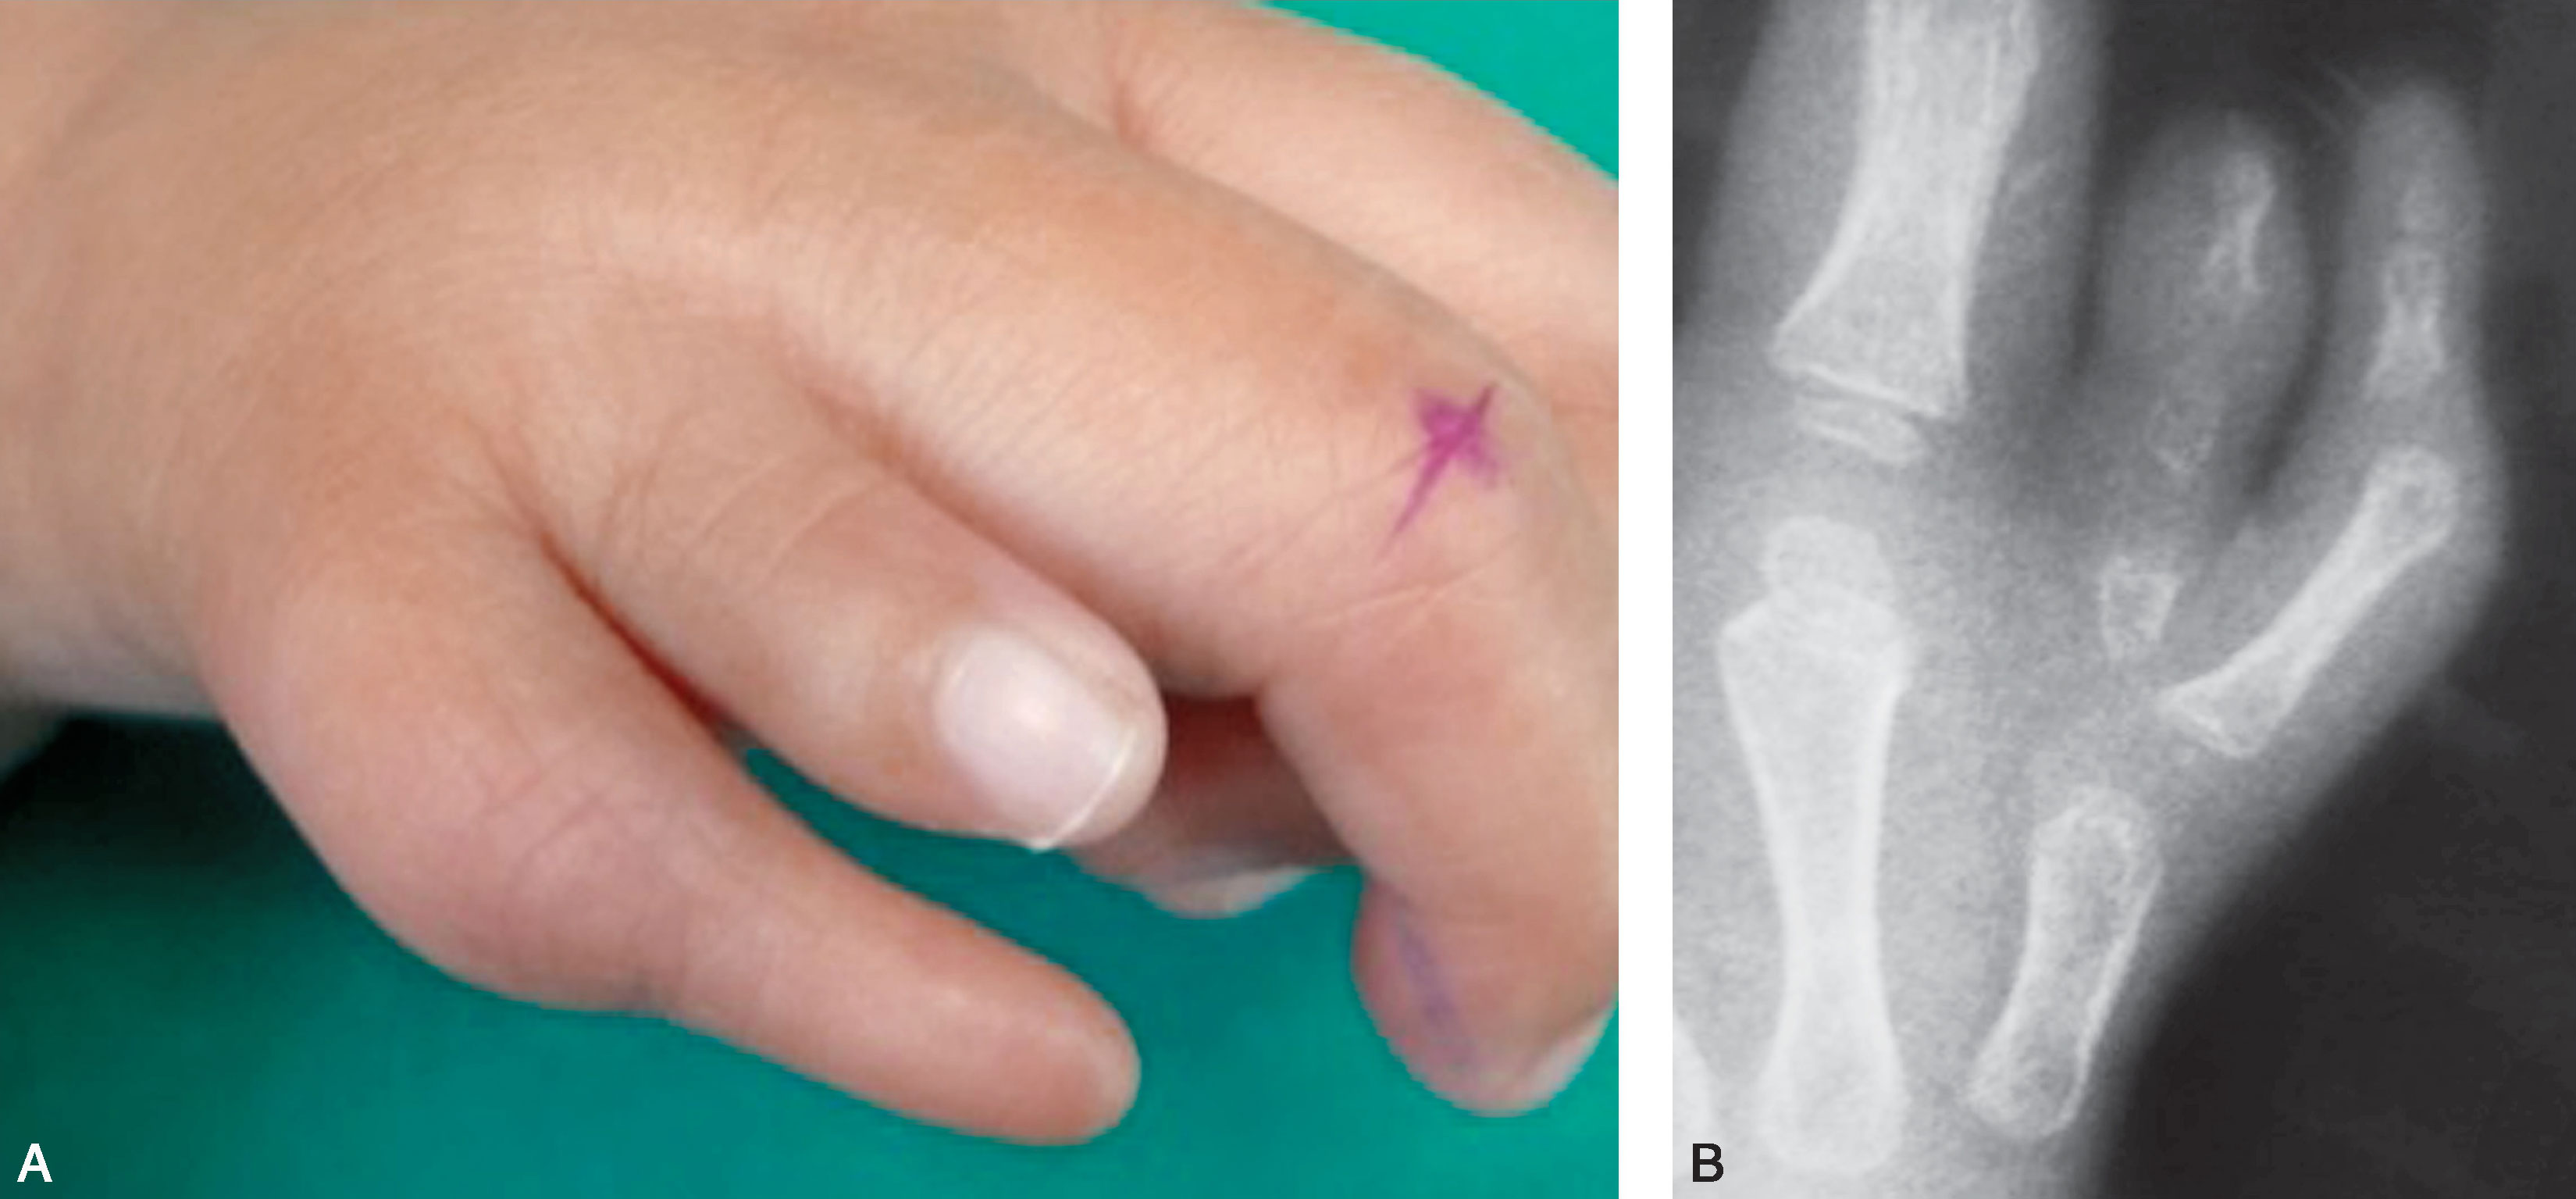

2.Ⅱ型 远节指骨完全分开,两个骨骺,近节指骨增宽,远端有两个关节面与近节指骨形成两个关节(图2-1-5~图2-1-11)。

图2-1-20 Ⅳ型病例1

A.左手多拇指,主、次拇指外形及大小相差较大;B.X 线片显示桡侧拇指骨关节结构明显发育不良,应切除桡侧拇指,术中重建保留的尺侧拇指的拇短展肌止点并紧缩掌指关节桡侧关节囊和侧副韧带